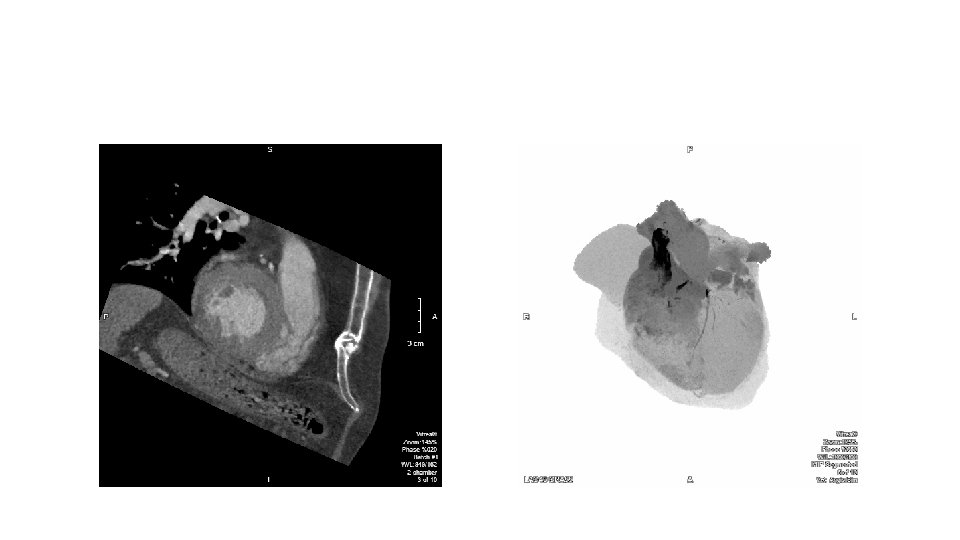

• TV assessment • severity of TR • Mechanism of • mode of leaflet coaptation, • degree of tricuspid annulus enlargement and tenting • TAPSE • 3 D-TEE • Cardiac CT • cardiac MRI

CT and MRI